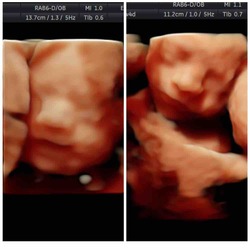

21 weken zwanger van een jongen en een meisje 馃挋馃挆 ben van mezelf slank gebouwd, maar ben inmiddels al 8 kg aangekomen. Persoonlijk vind ik het lichaam van een zwangere vrouw juist prachtig!

20 weken van een tweeeige tweeling 馃挄